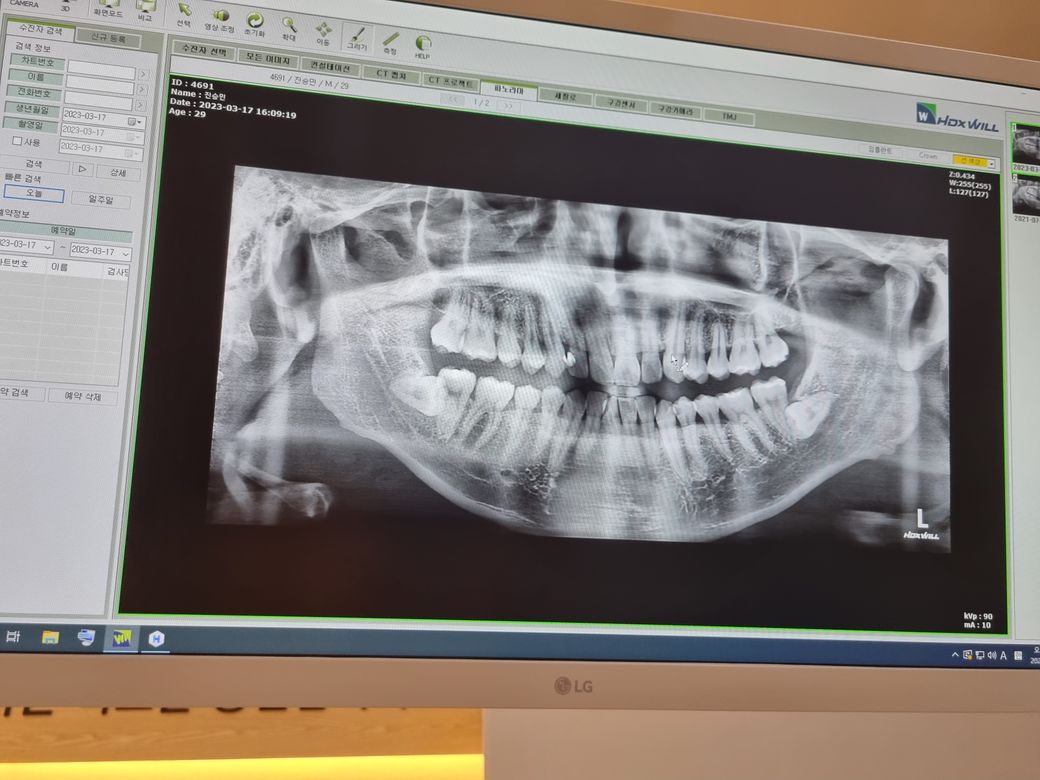

수평매복사랑니인데 이거 빼야 될까요?

우측 사랑니는 발치해서 위 사진이 현재 상태입니다.아래 사진은 원래 상태였구요.. 근데 우측 사랑니 발치회복후 좌측 사랑니 발치를 하려했는데 의사선생님이 극구 말리시네요ㅠㅠ 지금이 뽑을 적기같긴한데.. 발치시 많이 위험한 모양인가요? 어떻게 위험한가요?

도와주세요 제발.. 아래는 표시안된 깨끗한 사진입니다.

• 2번 째 사진

좌측 아래 사랑니는 깊이 매복되어 있으면 밑으로 신경관과 사랑니가 겹쳐 있습니다.

좌측 아래 사랑니는 깊이도 깊이지만 신경과 굉장히 가까워 보이네요. 신경손상 위험이 강해서 발치하지 말라고 하시는거 같습니다. 그리고 잇몸뼈 깊숙히 뭍혀 잇어서 발치를 안하셔도 크게 문제가 되진 않을것같습니다.